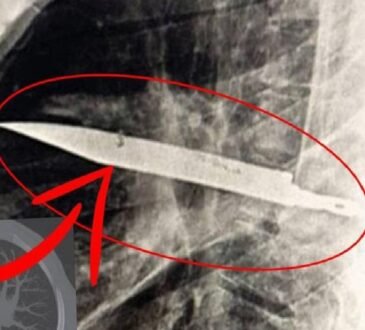

Günlük yaşamda en sık başvurulan ilaçlardan biri olan ağrı kesiciler, yanlış kullanımda ciddi sağlık risklerine yol açabiliyor. Uzmanlar, bilinçsizce kullanılan ağrı kesicilerin zamanla fayda yerine zarar verdiğini, hatta ağrıların asıl sebebine dönüşebileceğini belirtiyor.